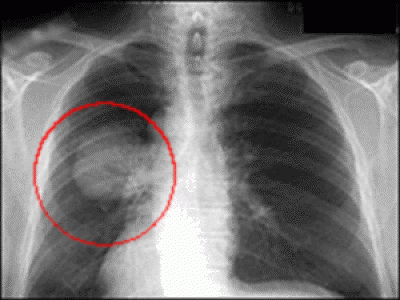

Найважливіший фактор — це стадія, на якій виявили рак. Рання діагностика часто рятує життя.

На стадії I, коли пухлина менша за горіх і не поширилась за межі легені, шанси на одужання значно вищі. Мій сусід, Василь Петрович, живе вже 7 років після операції на ранній стадії раку.

Статистика виживаності за стадіями

| Стадія | П’ятирічна виживаність |

|---|---|

| I | 60-80% |

| II | 30-50% |

| III | 10-30% |

| IV | менше 10% |

Ці цифри — не вирок, а статистика. За кожним відсотком стоять реальні люди, які борються і перемагають.